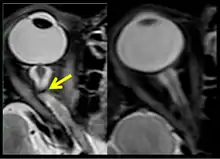

The sixth case of visual changes of an ISS astronaut was reported after return to Earth from a 6-month mission. When he noticed that his far vision was clearer through his reading glasses. A fundus examination performed 3 weeks postflight documented a grade 1 nasal optic-disc edema in the right eye only. There was no evidence of disc edema in the left eye or choroidal folds in either eye (Figure 13). MRI of the brain and eyes days postflight revealed bilateral flattening of the posterior globe, right greater than left, and a mildly distended right optic nerve sheath. There was also evidence of optic-disc edema in the right eye. A fundus examination postflight revealed a "new onset" cotton-wool spot in the left eye. This was not observed in the fundus photographs taken 3 weeks postflight.[4]